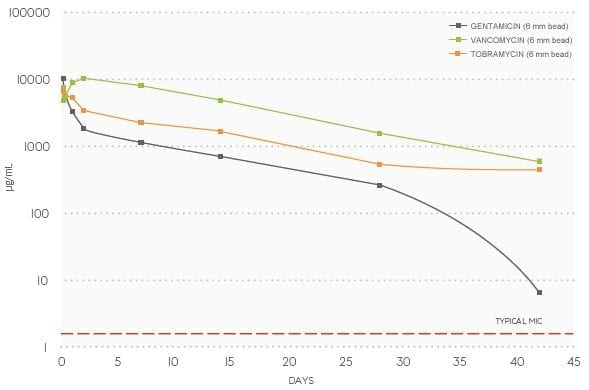

Antibiotic elution from STIMULAN Rapid Cure™9